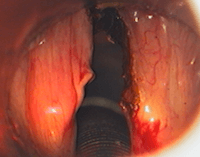

Intervention chirurgicale sous anesthésie générale: Laser CO2 (lumière rouge) des 2 cordes vocales pour myxœdème laryngé